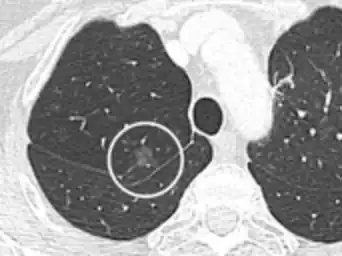

- Location: Upper lobe location is a risk factor for cancer, while a location close to a fissure or the pleura indicates a benign lymph node,[8] especially if having a triangular shape.[9]

- Margin morphology: a spiculated margin is a risk factor for cancer.[8] Benign causes tend to have a well defined border, whereas lobulated lesions or those with an irregular margin extending into the neighbouring tissue tend to be malignant.[10] In particular, spiculations are highly predictive of malignancy with a positive predictive value up to 90%.[9] Also, a "notch sign", which is an abrupt indentation of the nodule, increases the risk of cancer, but may also be found in granulomatous diseases.[9]

- Multiplicity: Where the presence of up to an additional 3 nodules has been found to increase the risk of cancer, but decrease in case of 4 or more additional ones, likely because it indicates a previous granulomatous infection rather than cancer.[8]